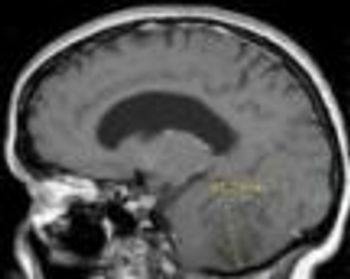

MRI is now central to the diagnosis of multiple sclerosis. Because of the modality’s high sensitivity to inflammation and demyelinating plaques, roughly 90% of all MS diagnoses are now based on MRI findings.

Sodium levels are known to be elevated inside the brain stem, cerebellum, and temporal poles early in the course of MS. This study showed total sodium concentrations to be significantly increased in advanced disease-particularly in normal-appearing brain tissues, concomitant with disability.